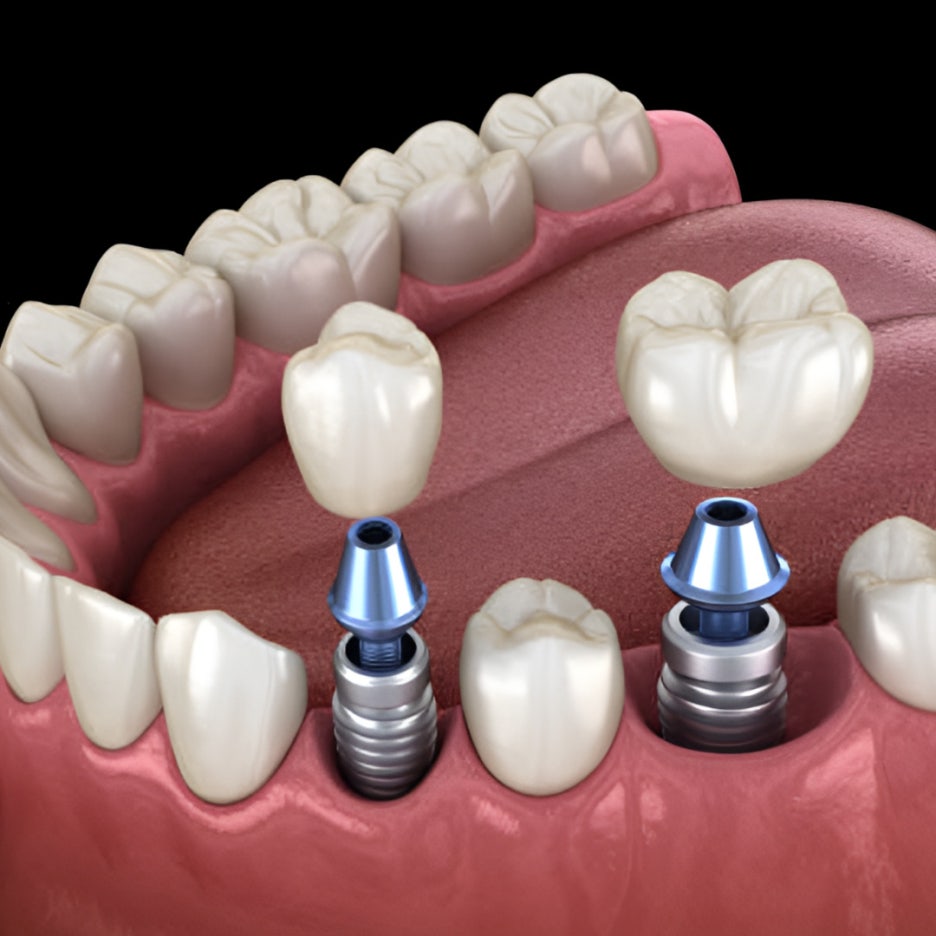

위와 같은 형태가 대표적인 ‘임플란트 브릿지’인데요. 치아 3개가 상실되었을 때, 2개만 심고 3개 치아 역할을 회복하는 모습입니다.

위 사진은 어금니 부위에 2개만 심고, 치아 3개의 역할을 복구한 모습입니다. ^^